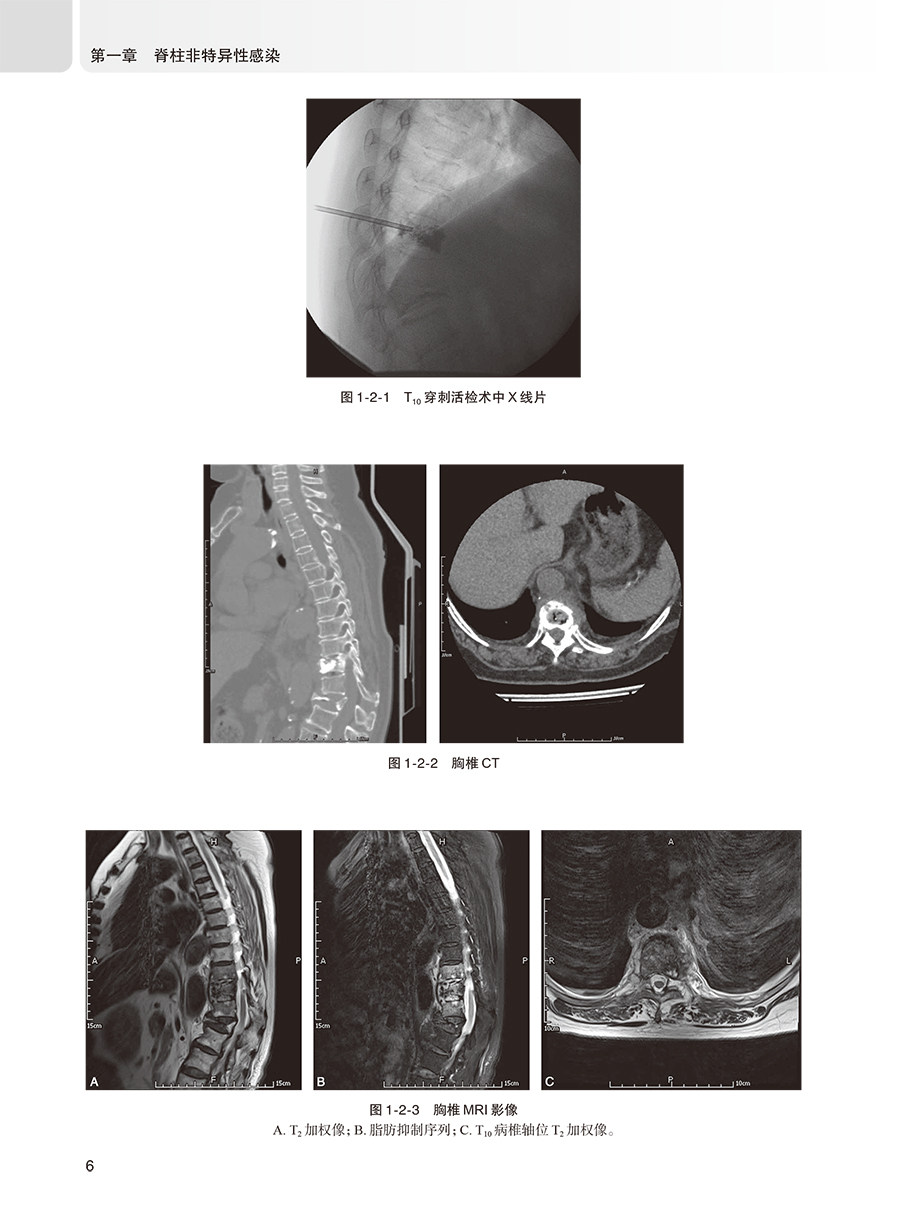

第二节 脊柱表皮葡萄球菌感染 4